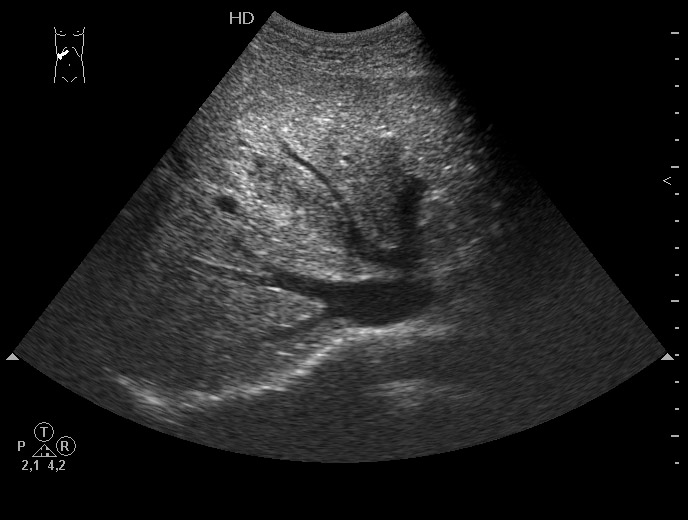

Выставляю картинку, по которой можно установить диагноз практически без дополнительных данных.

гипоэхогенная полоска в печени...может быть разрыв

Все верно, разрыв печени плюс жидкость в боковом синусе плевральной полости.

Ультразвуковая семиотика разрыва довольно типична. Разместить эту сонограмму решил после того, как увидел протокол из одной авторитетной клиники, где гемангиома была трактована как разрыв печени и внутрипеченочная гематома.